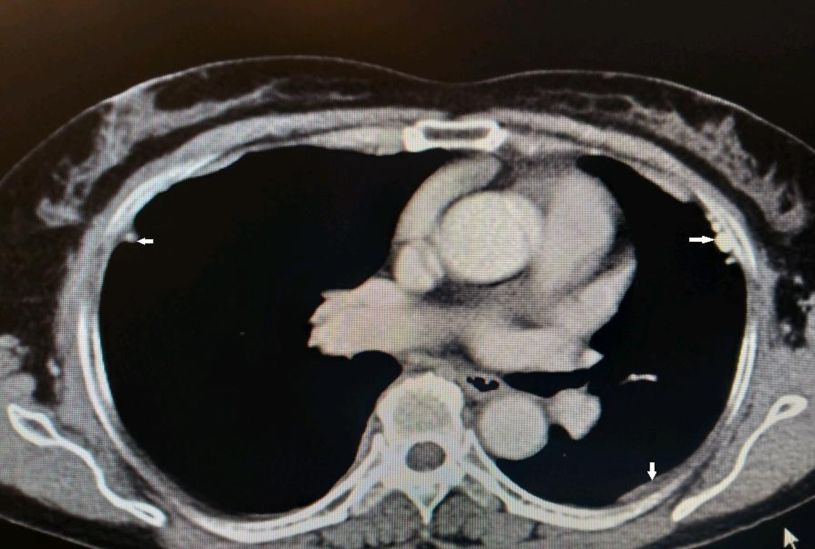

图示:患者两侧胸膜可见结节、钙化影(白箭)

到目前为止,除了胸腔积液之外,仔细阅读该患者胸部CT发现该患者的另外一个特点就是胸膜增厚、结节、钙化影。通过这一线索,不排除有胸膜来源疾病的可能。

所以,进一步的检查就选择了胸腔镜对胸膜进行活检。2018-11-28于全麻下行经胸腔镜胸膜活检术,镜下见脏层胸膜两枚小结节,壁层胸膜见散在片状及结节状白色钙化灶,部分胸膜肿胀隆起,触之质脆,分别于病灶处钳取多块组织送病理学检查。